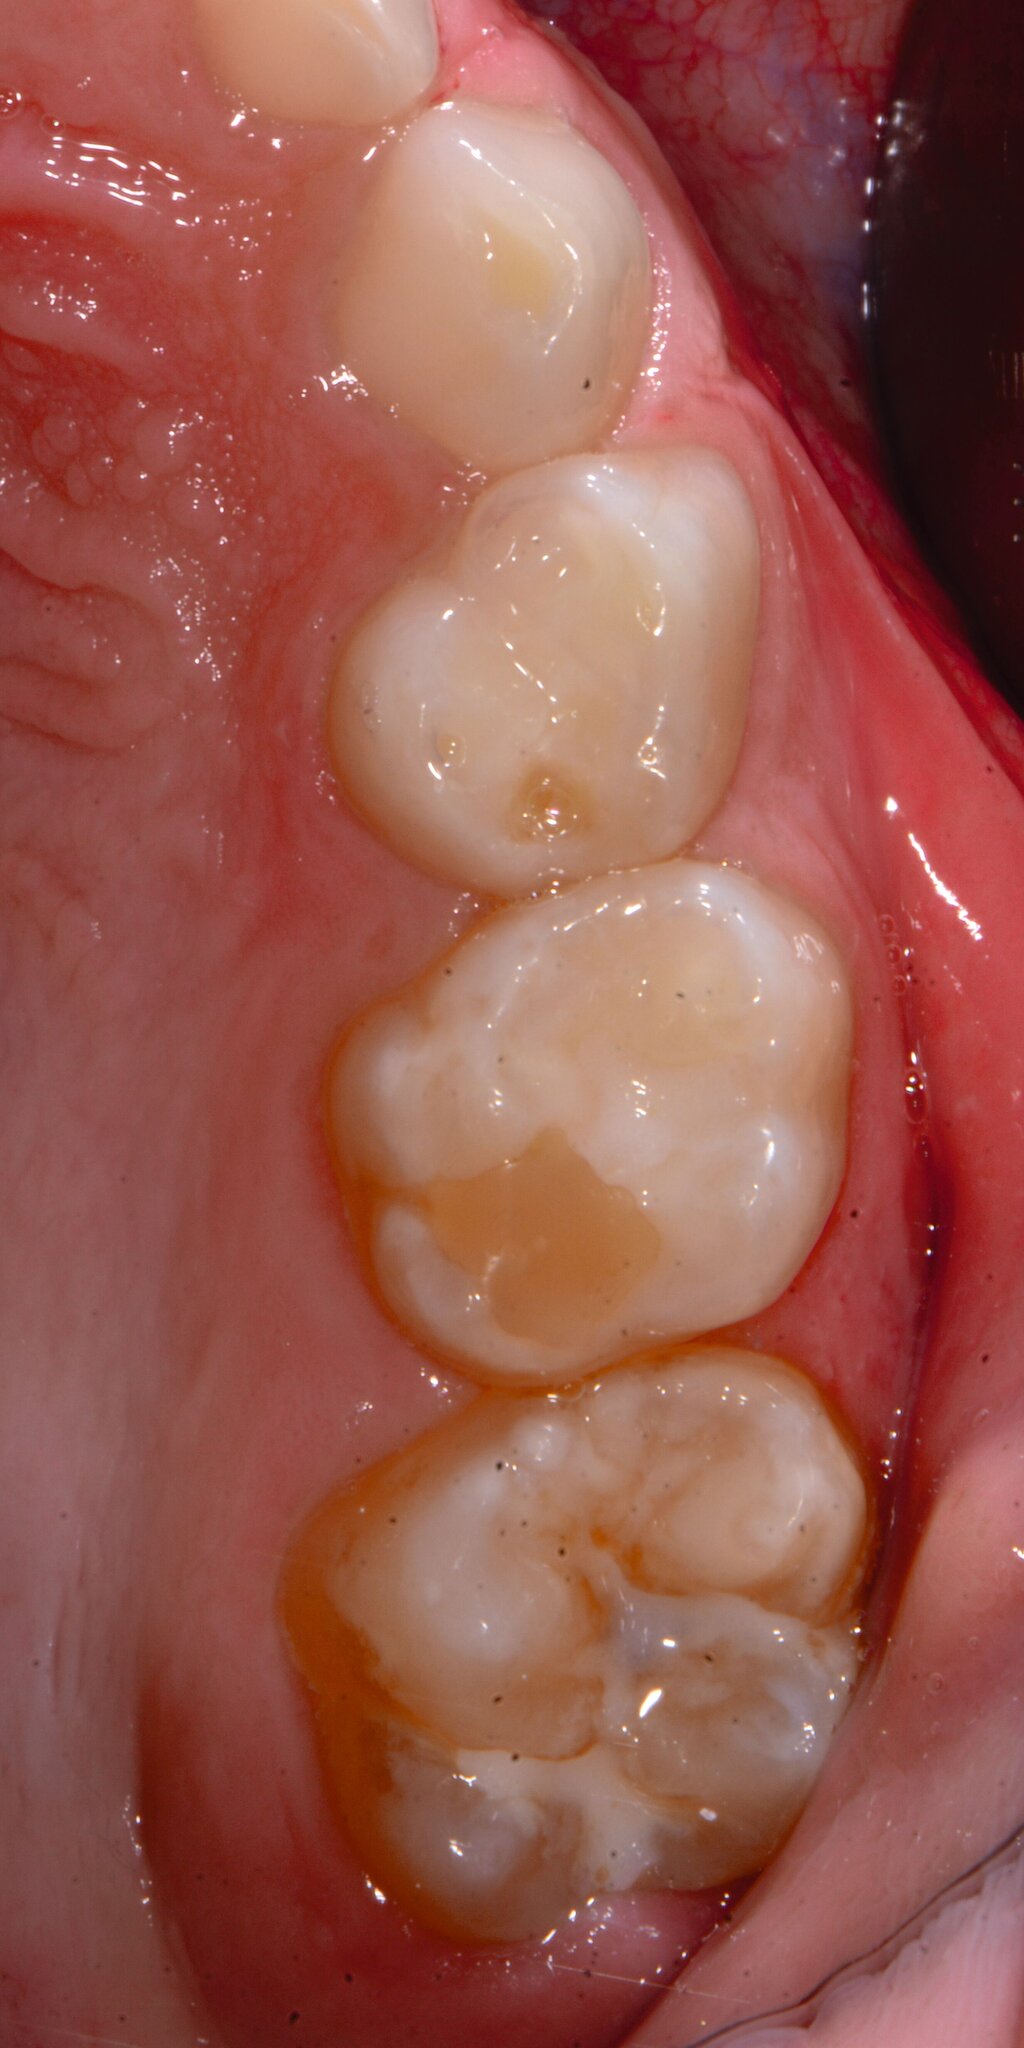

Das klinische Erscheinungsbild an bleibenden Zähnen zeigt typischerweise weißlich-gelbe bis gelblich-braune Opazitäten, die zumindest in einigen Bereichen durch eine scharfe Abgrenzung (engl.:„demarcated opacities“) zum gesunden Zahnschmelz charakterisiert sind (Abbildungen 3 und 4). Die abgegrenzten Hypomineralisationen befinden sich mehrheitlich im Bereich der inzisalen Kronenhälfte unabhängig von dem Auftreten an Front- oder Seitenzähnen. Die Ausprägung am Zahn kann dabei auf einzelne Areale oder Höcker begrenzt sein.

Bei einer schwerwiegenderen Ausprägung sind Zahnflächen vollständig betroffen, mitunter alle Zahnflächen an einem Zahn. Die Verteilung in der Dentition beziehungsweise an den Indexzähnen ist gleichermaßen variabel und betrifft nicht nur die Defektgröße, sondern auch die Farbe und Festigkeit. Was die Festigkeit betrifft, gilt als die Faustregel: Je dunkler die Farbe des Schmelzes, umso weicher beziehungsweise poröser und damit minderwertiger wird dessen Qualität sein. Damit reduziert sich seine kaufunktionelle Belastungsfähigkeit, was insbesondere an ersten bleibenden Molaren von klinischer Relevanz ist.

An umfangreich hypomineralisierten Zähnen können Schmelzeinbrüche (engl.: „enamel breakdown“ oder „enamel desintegration“, Abbildung 5) auftreten [Lygidakis et al., 2010; 2022]. Da diese oftmals die Folge einer fehlenden Belastungsfähigkeit des Zahnschmelzes sind und erst nach der Einstellung der Zähne in die Okklusion auftreten, werden sie auch als posteruptive Schmelzeinbrüche bezeichnet. Sie sind häufig im Bereich der Kauflächen beziehungsweise Höcker der Molaren zu finden, führen zur Dentinexposition und damit einhergehend zu ausgeprägten Hypersensitiven insbesondere bei Kindern, deren Zähne gerade erst durchgebrochen sind [Linner et al., 2021].

Für die Dokumentation und Klassifikation der MIH wurden verschiedene Systeme vorgeschlagen. Als historisch und veraltet gilt der (modifizierte) DDE-Index. Demgegenüber haben die Kriterien der EAPD – abgegrenzte Opazitäten (Abbildung 3 und 4), Schmelzeinbrüche (Abbildung 5), atypische Restaurationen (Abbildung 6) – mittlerweile die weiteste Verbreitung gefunden. Diese wurden 2003 erstmals zur Beschreibung der MIH auf empirischer Basis publiziert [Weerheijm et al., 2003] und den Jahren 2010 und 2022 im Rahmen der damaligen MIH-Workshops bestätigt [Lygidakis et al., 2010; 2022].